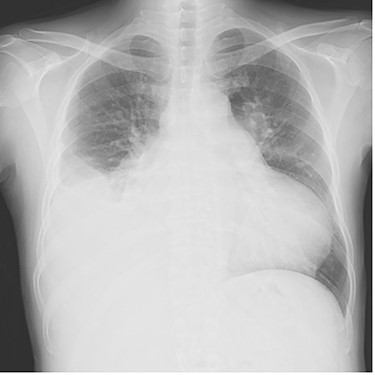

Chest radiography showed an enlarged heart with a cardiothoracic ratio of 73% and right pleural effusion (Fig. 1). Laboratory test results were as follows: blood urea nitrogen, 48.1 mg/dl; creatinine, 1.96 mg/dl; total bilirubin, 2.7 mg/dl and N-terminal prohormone of brain natriuretic peptide: 3043 pg/ml. Transthoracic echocardiography revealed ejection fraction of 49%, severe AR, mild to moderate mitral regurgitation, severe pulmonary regurgitation and mild to moderate tricuspid regurgitation. The pulmonary valve’s maximum pressure gradient had decreased from 31 mmHg 8 months previously to 5 mmHg. The diameter of the ascending aorta was 39.2 mm, sinotubular junction was 36.1 mm and Valsalva sinus was 47.4 mm. Cardiac catheterization showed no significant coronary artery stenosis.

Plain chest radiograph of the first outpatient visit after discharge from the hospital.